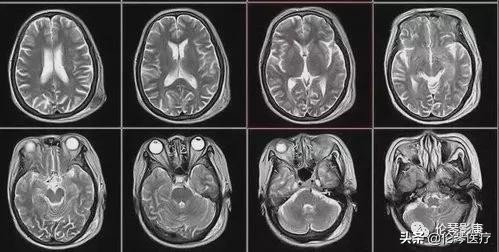

磁共振检查是一项比较常见的检查,它能够帮助扫描身体内一些器官以及骨骼来帮助确诊疾病,可是,常有一些人在需要进行磁共振检查时不知道该准备什么,常因准备不充分带来了不好的体验。今天影领医学影像诊断中心和大家聊聊磁共振检查的八大常见问题。